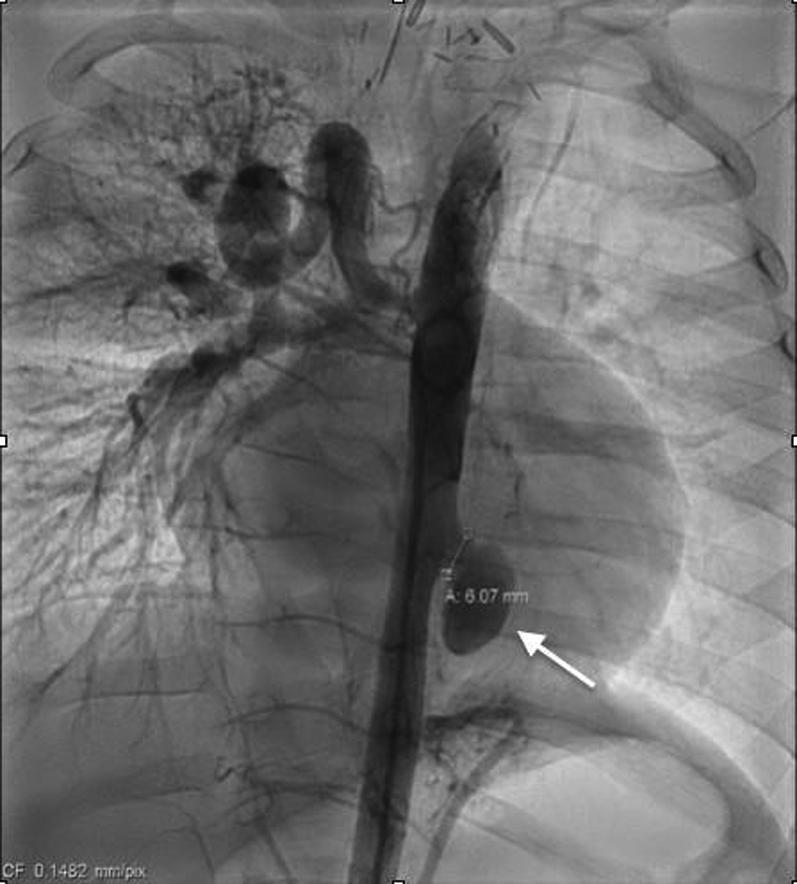

Pediatric aortic pseudoaneurysms are rare and can result in life-threatening sequelae. We describe 2 cases of exclusion of descending thoracic aortic pseudoaneurysm by different approaches, chosen based on the anatomy and cause of the lesions. ().

小儿主动脉假性动脉瘤较为罕见,可导致危及生命的后遗症。我们描述了2例通过不同方法排除降主动脉假性动脉瘤的病例,这些方法是根据病变的解剖结构和病因选择的。()